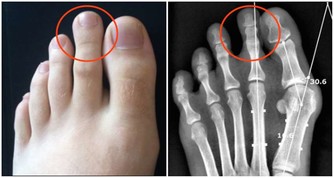

另一方面,攝入大量果糖還可引起肥胖、糖尿病、高尿酸血症、高血脂等疾病,它們和高血壓是一家親,常常誘發或加重高血壓及其他心血管疾病。